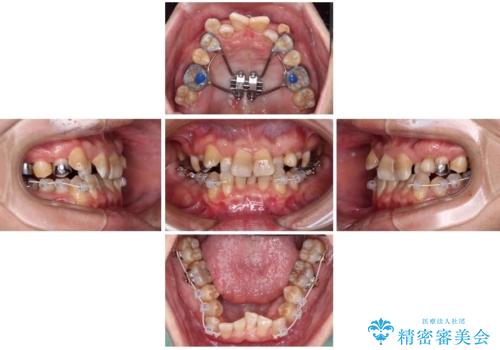

全体的なデコボコが気になる。拡大装置を併用したワイヤー矯正

- 上下の前歯のデコボコを改善したいと来院された患者様です。

上顎の歯列幅が狭く、それによって歯が並ぶスペースが不足しています。

また下顎の歯列幅も制限され、内側に歯が倒れています。

それらを改善するため上顎に拡大装置を用いて、審美装置にてワイヤー矯正を行いました。

左上の乳犬歯は当初保存する計画でしたが、虫歯が大きいため抜歯になり、患者様の希望によりブリッジにしました。